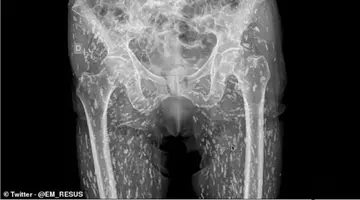

Infecţia urinară, calculii la rinichi sau chiar paralizia, aceste probleme serioase de sănătate pot fi rezolvate cu masajul cu pietre de jad. De peste 5000 de ani, chinezii folosesc jadul pentru ceea ce ei numeau “puterile sale magice” şi, observându-i efectele terapeutice pentru calculii renali, au numit-o “piatra rinichilor”.

Ca şi beneficii asupra corpului uman: eliminare calculi renali (nisip şi pietre la rinichi), echilibrări hormonale, stimularea circulaţiei sangvine, calmare, somn mai liniştit, ajută împotriva insomniilor. Nicoleta Magargiu, Manager Casa Jad, ne răspunde la câteva întrebări menite să ne lămurească cu priviri la contraindicaţiile şi beneficiile acestui tratament.

Terapia cu pietre de jad şi raze infraroşii este contraindicată femeilor însărcinate datorită faptului că prin căldura degajată de pietrele de jad se produce dilataţie, ori nu ne dorim asta decât în momentul naşterii iar atunci, un aparat cu pietre de jad încălzit este într-adevăr recomandat pentru a grăbi dilataţia colului. Persoanelor cu osteoporoză gravă, atunci când există risc de fracturi pentru că oasele sunt fragile şi masajul pe pietre din jad masiv devine contraindicat. Persoanelor cu tijă metalică pe coloana vertebrală pentru că, de la caldură, aceasta s-ar putea încălzi. Persoanelor cu inflamaţii acut supurative. Persoanelor cu hipertensiune gravă – datorită căldurii, fluxul sangvin creşte şi tensiunea arterială poate creşte şi ea.